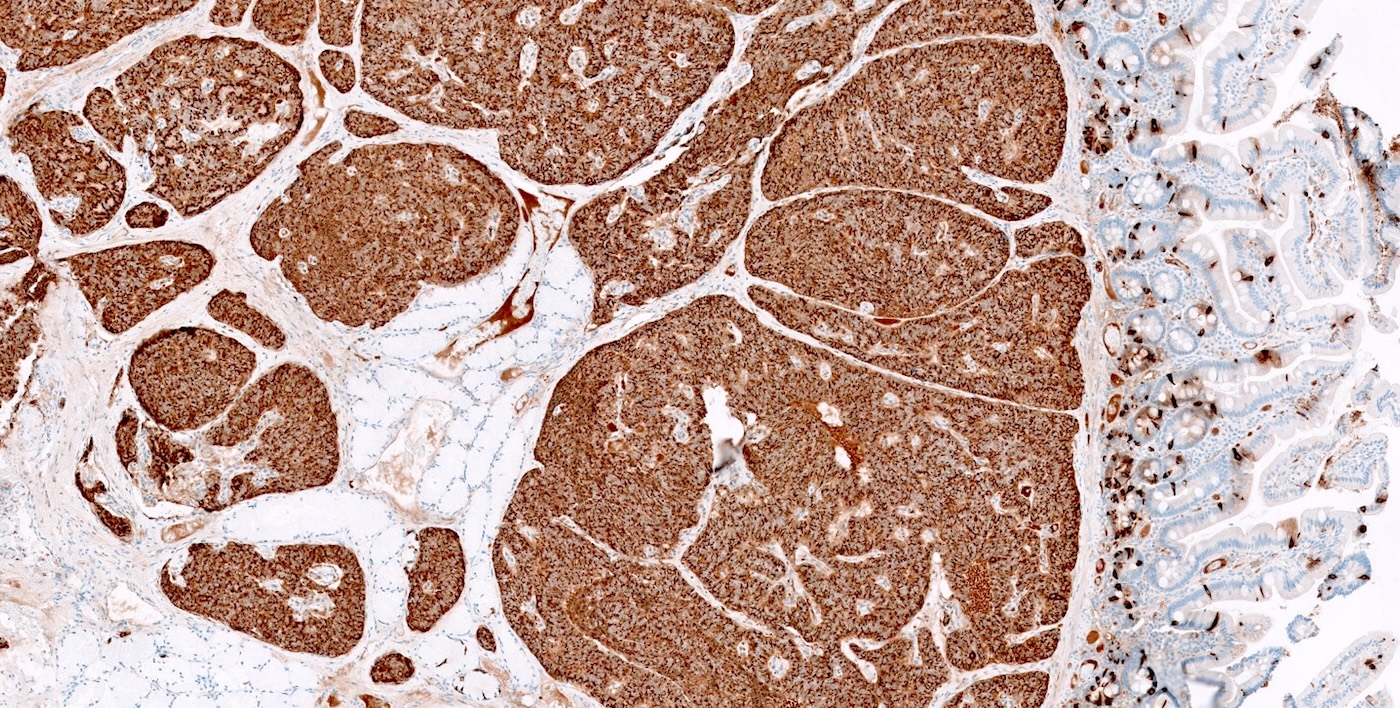

- Immunohistochemical staining positive for chromogranin A, synaptophysin and neuroendocrine markers (Arch Pathol Lab Med 2025 Mar 4 [Epub ahead of print])

- Multiple pancreatic microadenomas or microtumors are a common feature of MEN1 associated PanNETs and serve as a useful clue to the diagnosis of MEN1

- Immunohistochemical analysis may reveal nuclear menin loss in MEN1 associated tumors (Am J Surg Pathol 2023;47:785, Front Endocrinol (Lausanne) 2023;14:1221514)

- Comment: The histologic findings, along with immunohistochemical studies (positive synaptophysin and chromogranin staining and a Ki67 proliferative rate of 1% in tumor cells), confirm the diagnosis of a well differentiated pancreatic neuroendocrine tumor (grade 1). The patient has a known history of parathyroid hyperplasia and a pituitary adenoma. The presence of primary hyperparathyroidism, pancreatic neuroendocrine tumors and pituitary adenoma is consistent with the classic triad of multiple endocrine neoplasia type 1 (MEN1).